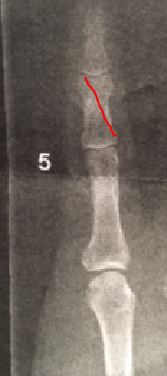

spricka